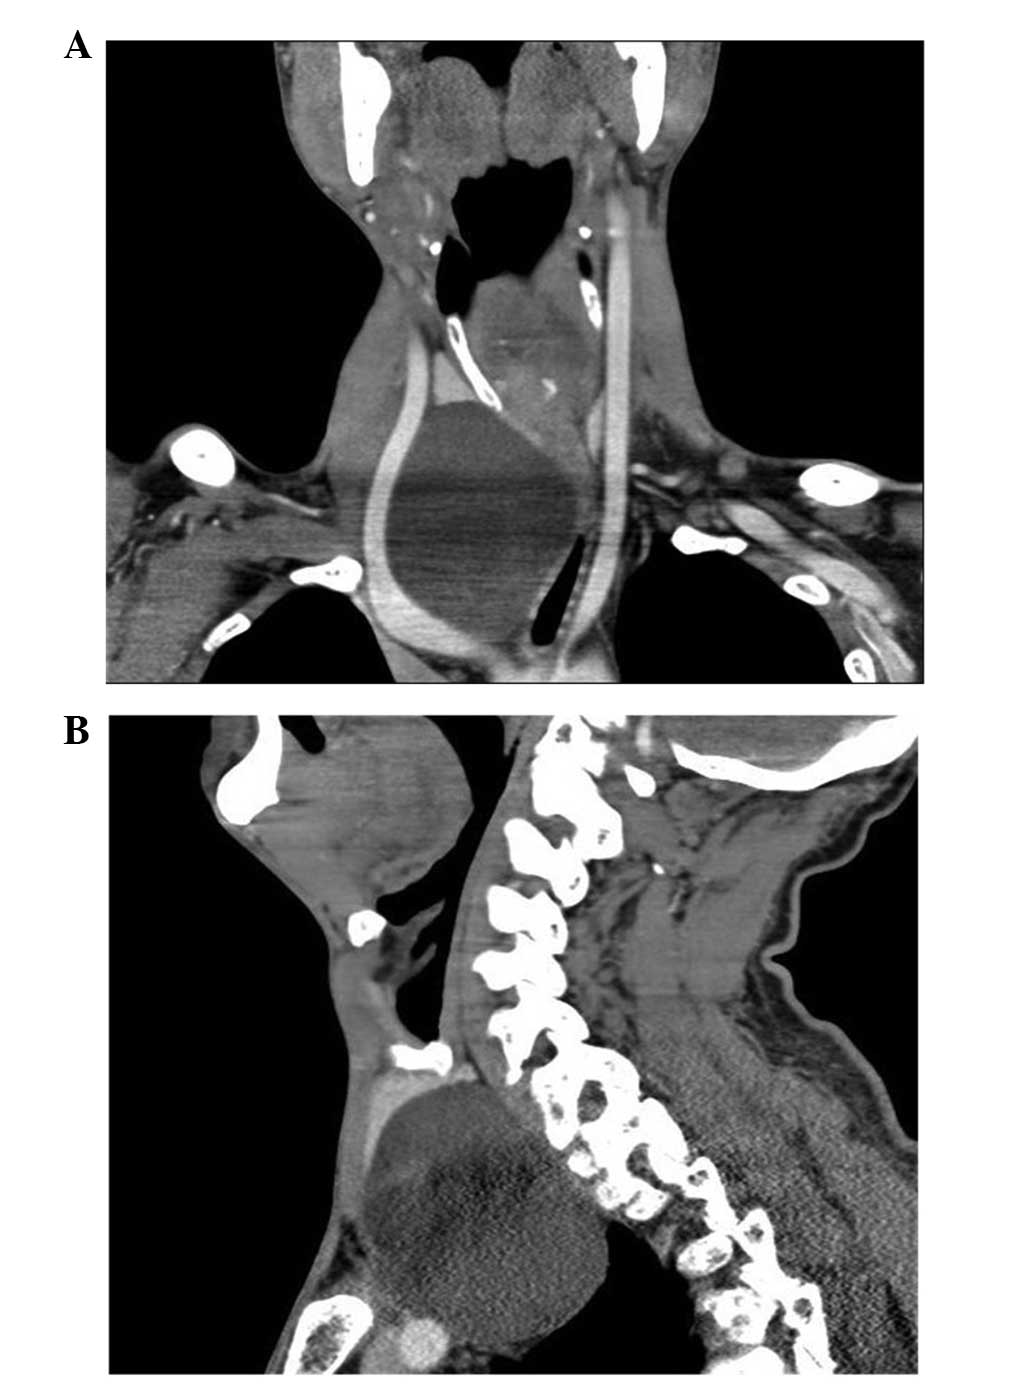

The physical examination revealed a palpable round-shaped mass in the right thyroid lobe. The ultrasound (Philips iU22; Philips Healthcare, Andover, MA, USA) showed a 8.4×5.7×3.6-cm cystic mass attached to the right thyroid lobe (Fig. 1). A neck and chest computed tomography (CT; LightSpeed Pro32 spiral scanner with a layer thickness of 5 mm; GE Healthcare Bio-Sciences, Pittsburgh, PA, USA) scan was performed with contrast media, which showed the presence of a large neck and mediastinal mass (9.0×6.0 cm) with no contrast enhancement, causing right anterolateral displacement of the large vessels and left anterolateral displacement of the trachea (Fig. 2). The serum calcium and PTH concentrations were measured and identified as normal, at 2.26 mmol/l (normal range, 2.03–2.54 mmol/l) and 37.98 pg/ml (normal range, 15–65 pg/m), respectively. A fine-needle aspiration biopsy (FNAB) was performed, and the content obtained from the cyst was a colorless crystal clear fluid, suggesting that the mass was a PC. The levels of PTH in the aspirated fluid were elevated (308 pg/ml; normal serum range, 10–65 pg/ml). A cytological examination of the material that was obtained following centrifugation of the fluid showed a few epithelial cells that possibly belonged to the parathyroid tissue. Based on the aforementioned findings, the diagnosis of the giant cyst was of a non-functional PC.

Figure 2.

Neck and chest computed tomography scans with contrast media revealing a large mediastinal mass (9×6 cm) without contrast enhancement causing the right anterolateral displacement of large vessels and the left anterolateral displacement of the trachea. (A) Coronal scanning. (B) Sagittal scanning.